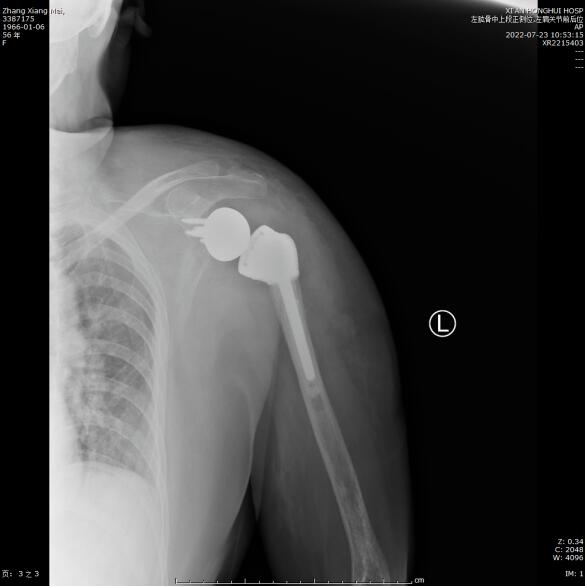

术后患者状况良好,第二天即可开始下地活动,肩关节也可以做一些简单的前后运动,X光片显示肩关节假体在位良好,目前患者已康复出院。